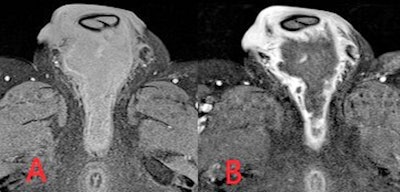

The MRI sequences employed in suspected soft tissue infection typically include T2, a fluid-sensitive sequence such as short-tau inversion recovery (STIR), and unenhanced and postcontrast T1. Diffusion-weighted imaging (DWI) may be added in certain cases, such as to assess for abscess formation, and fat-saturated T2 or enhanced T1 sequences can be used to improve the delineation of inflammation, Delaney and colleagues continued.

A gradient echo sequence may be added in more severe cases with suspected hemorrhage or necrotizing fasciitis. In cellulitis, high T2 and STIR signal intensity with corresponding T1 signal intensity of the subcutaneous tissues with overlying skin thickening is seen, and there is enhancement following gadolinium administration.

"MRI provides the most accurate evaluation of the extent of deeper infections and of surrounding soft tissue anatomy and can also assess for associated abnormality of adjacent bones or joints," they wrote. "On MRI, soft tissue abscesses demonstrate internal high T2 and STIR signal with corresponding low T1 signal, peripherally enhancement following intravenous gadolinium administration and restrict diffusion on DWI."